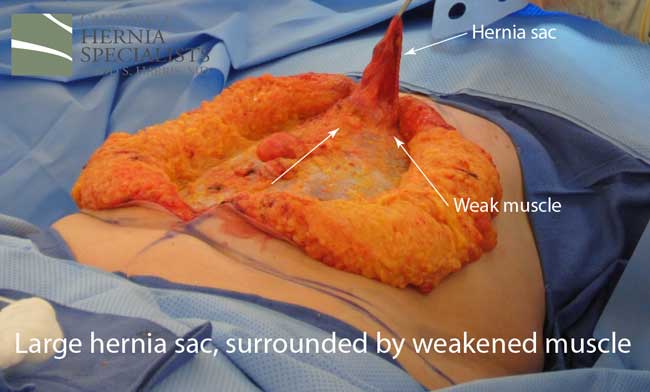

This initial CAT scan image shows why the hernia repair continued to fail. There is very weakened muscle in the middle of the abdomen with most of the healthy muscle several inches away on each side. More likely than not, the prior surgeon simply sewed the meshes into this unhealthy layer of fascia instead of bringing together the normal, healthy muscle.

After this CT scan was obtained, a lengthy discussion with the patient was undertaken to explain the reasons for the prior hernia repair failures, and to explain all the options. By simply returning to the operating room and putting in more mesh, and sewing it to unhealthy muscle, we would not be actually repairing the hernia.

The more complete approach would be to bring healthy muscle together at the mid line. Only after the muscle is repaired completely, can a mesh be used to SUPPORT the muscle repair. Meshes should not be considered a bridge from healthy muscle to healthy muscle. Instead mesh should be used as a reinforcement of a correct hernia repair.

This technique requires more surgical time, recovery time, and usually several days in the hospital. However, this patient chose to proceed with the open hernia repair. Below are some of the pictures from his surgery as well as post operative CT scan image and photos of the patient.